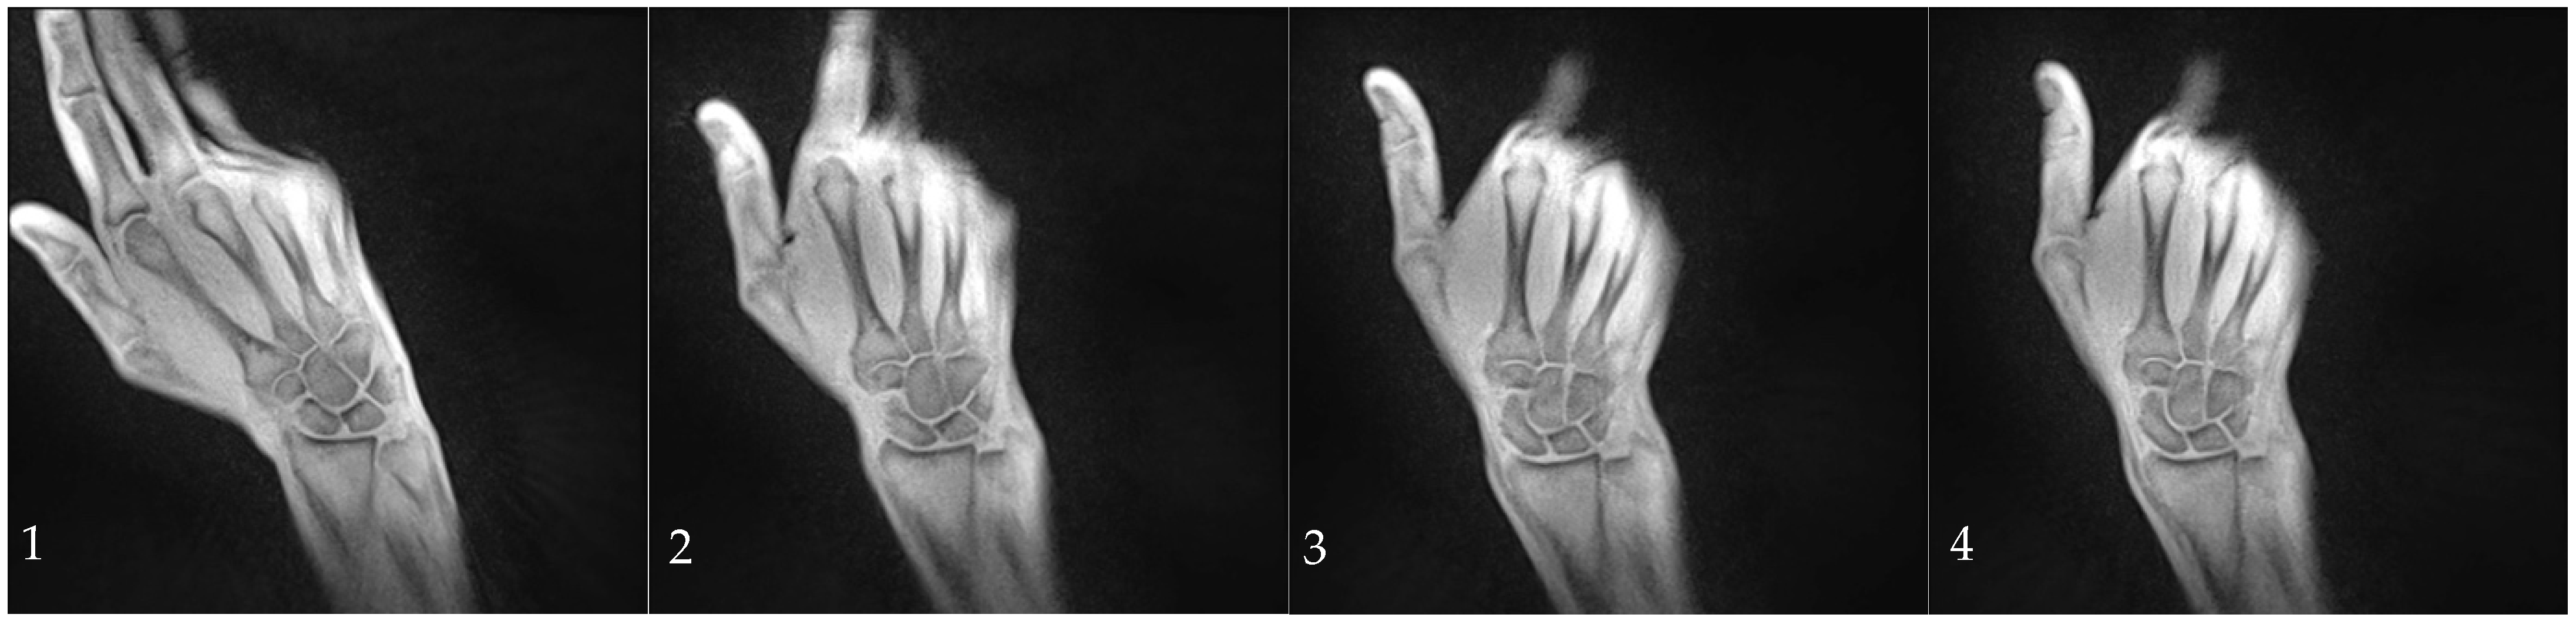

The SL distance was measured at three different positions with the distal, medial, and proximal bone points of the scaphoid and lunate serving as the anatomical landmarks. (Figure 2). Measurements were performed on both static and dynamic images.

Figure 2. Measurement of the SLJW in three positions: at the proximal landmark (red), the medial landmark (green) and the distal landmark (yellow).